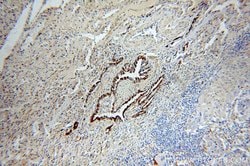

This antibody is specifically against KRT7.

Cytokeratin 7 blocks interferon-dependent interphase and stimulates DNA synthesis in cells. Involved in the translational regulation of the human papillomavirus type 16 E7 mRNA (HPV16 E7).Specifications

| Immunocytochemistry, Immunofluorescence, Immunohistochemistry (Paraffin), Immunoprecipitation, Western Blot | |